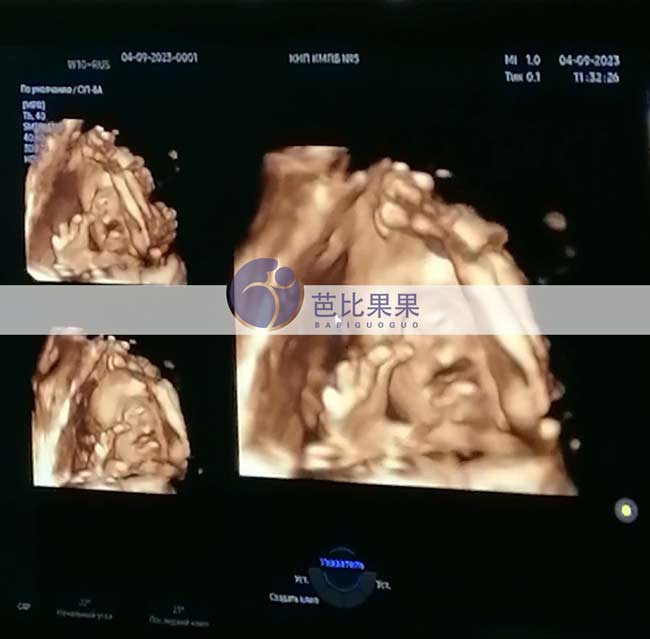

L先生的乌克兰试管妈妈做四维彩超检查,胎儿数据正常

L先生家的乌克兰试管妈妈到医院做了四维彩超检查,胎儿身体各项数据都发育正常,彩超下可见宝宝很活泼~